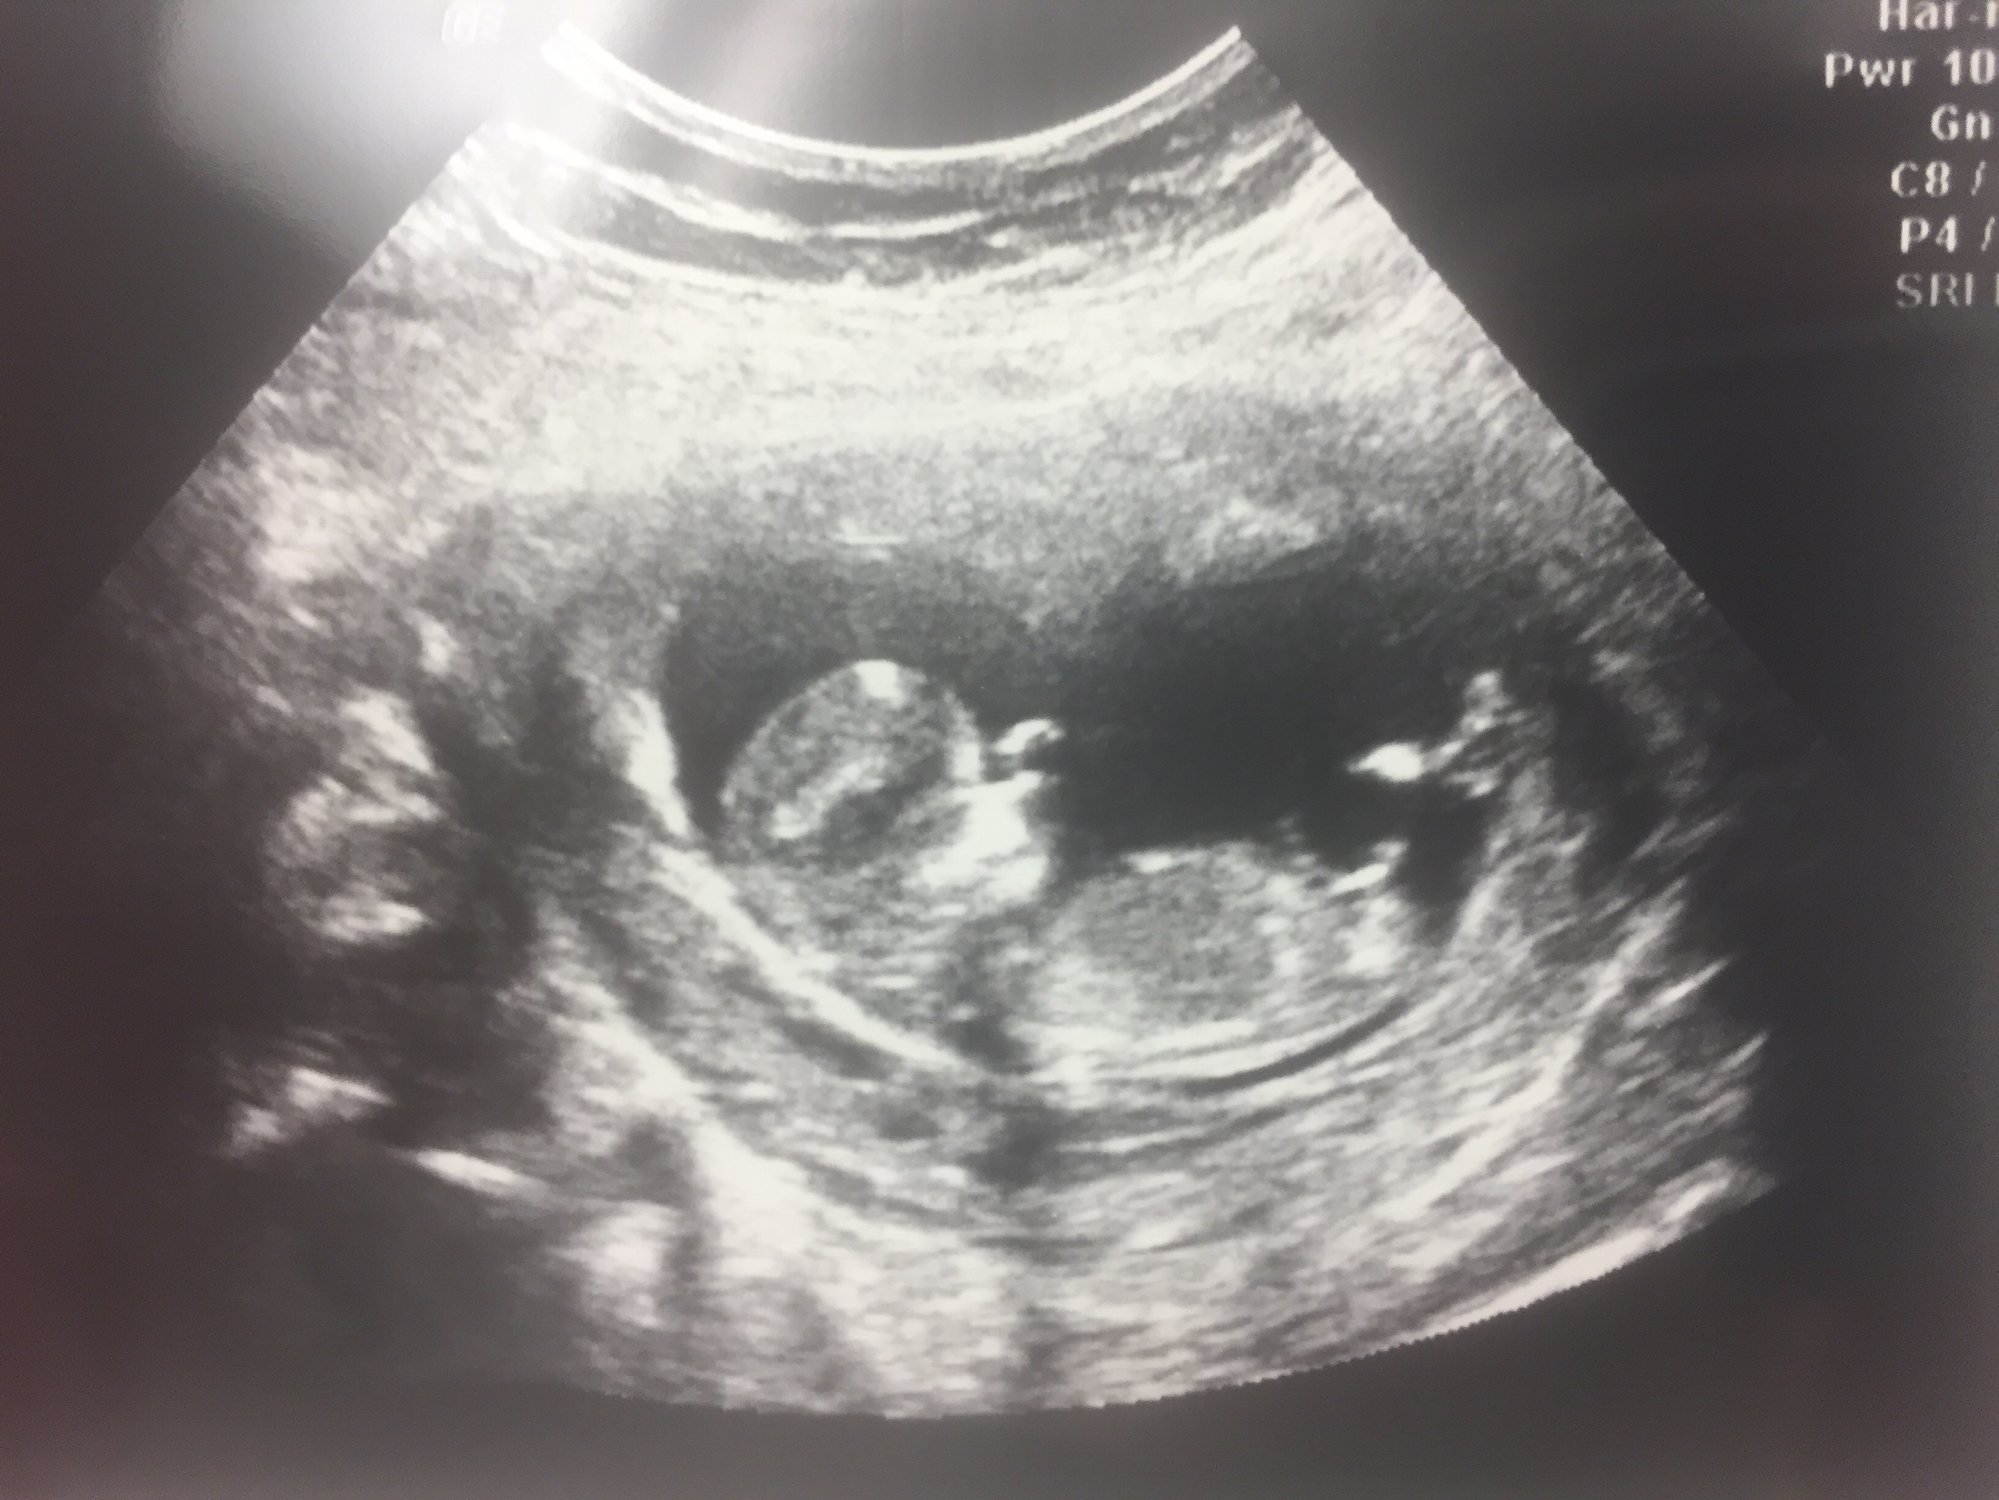

Hi guys, I've already posted my ultrasound, but I have a question that I was wondering if any of you knew the answer to. What is the other black space on the right side? I'm just curious as to what the heck it is haha btw this was an internal ultrasound.

@merrylea I didn't notice it until after I got home, but I was a little curious about that too. You can see that little piece coming down in both of the pictures I have. She didn't mention anything during the ultrasound and didn't look around after she found the baby. I'm assuming because this was my second ultrasound she didn't think to look for another one. I'm guessing there's just the one in there, but I won't be able to find out until December 19! It's quite a big space for just one